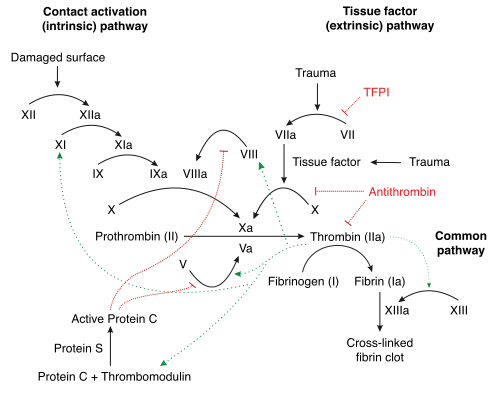

Under homeostatic conditions, the body is maintained in a finely tuned balance of coagulation and fibrinolysis. The activation of the coagulation cascade yields thrombin that converts fibrinogen to fibrin; the stable fibrin clot being the final product of hemostasis. The fibrinolytic system then functions to break down fibrinogen and fibrin. Activation of the fibrinolytic system generates plasmin (in the presence of thrombin), which is responsible for the lysis of fibrin clots. The breakdown of fibrinogen and fibrin results in polypeptides called fibrin degradation products (FDPs) or fibrin split products (FSPs). In a state of homeostasis between clot formation and clot dissolution, the presence of plasmin is critical, as it is the central proteolytic enzyme of coagulation and is necessary for the breakdown of fibrin clots, or fibrinolysis.[11]

In DIC, the processes of coagulation and fibrinolysis are dysregulated, and the result is widespread clotting with resultant bleeding. Regardless of the triggering event of DIC, once initiated, the pathophysiology of DIC is similar in all conditions. One critical mediator of DIC is the release of a transmembrane glycoprotein called tissue factor (TF). TF is present on the surface of many cell types (including endothelial cells, macrophages, and monocytes) and is not normally in contact with the general circulation, but is exposed to the circulation after vascular damage. For example, TF is released in response to exposure to cytokines (particularly interleukin 1), tumor necrosis factor, and endotoxin.[12] This plays a major role in the development of DIC in septic conditions. TF is also abundant in tissues of the lungs, brain, and placenta. This helps to explain why DIC readily develops in patients with extensive trauma. Upon exposure to blood and platelets, TF binds with activated factor VIIa (normally present in trace amounts in the blood), forming the extrinsic tenase complex. This complex further activates factor IX and X to IXa and Xa, respectively, leading to the common coagulation pathway and the subsequent formation of thrombin and fibrin.[7]

Activation of the intrinsic and extrinsic coagulation pathways causes excess thrombus formation in the blood vessels. Consumption of coagulation factors due to extensive coagulation in turn causes bleeding.[14][15]